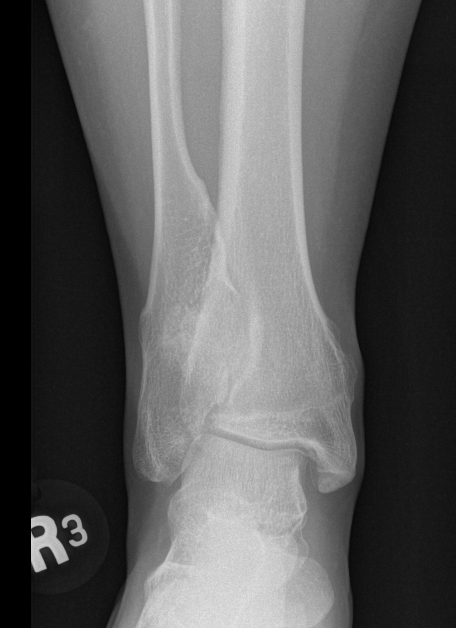

Ankle

- valgus

- fibular shortening with valgus distal tibia

- wedge-shaped distal tibial epiphysis

- leads to valgus talar tilt in abnormal mortise

Ankle mult OC 1Ankle mult OC 2